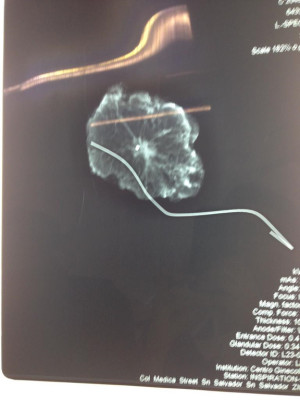

Fibroma gigante